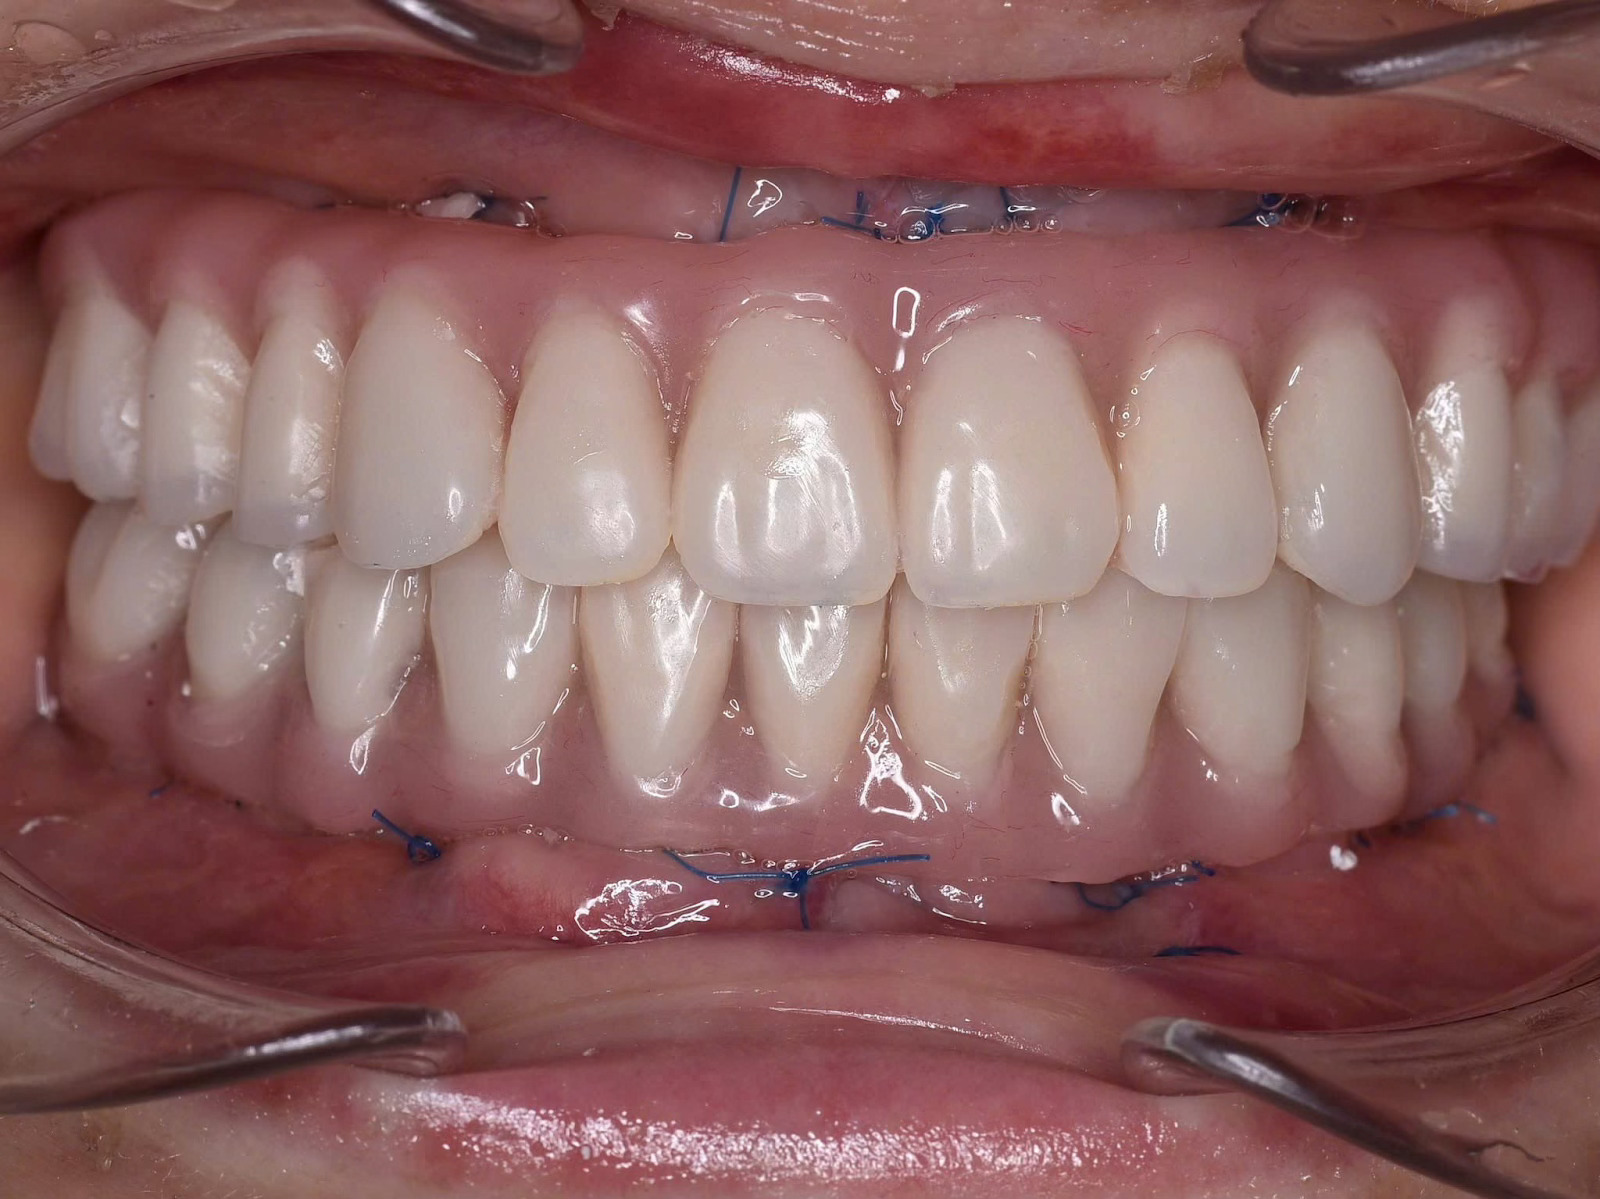

![]() |

| 670294401_4299763916938557_6629409047496729875_n |

| Cấy ghép Implant toàn hàm và phục hình tức thì sau 24h tại Nha Khoa Như Ngọc (21 Trần quang diệu, Hà Nội) |